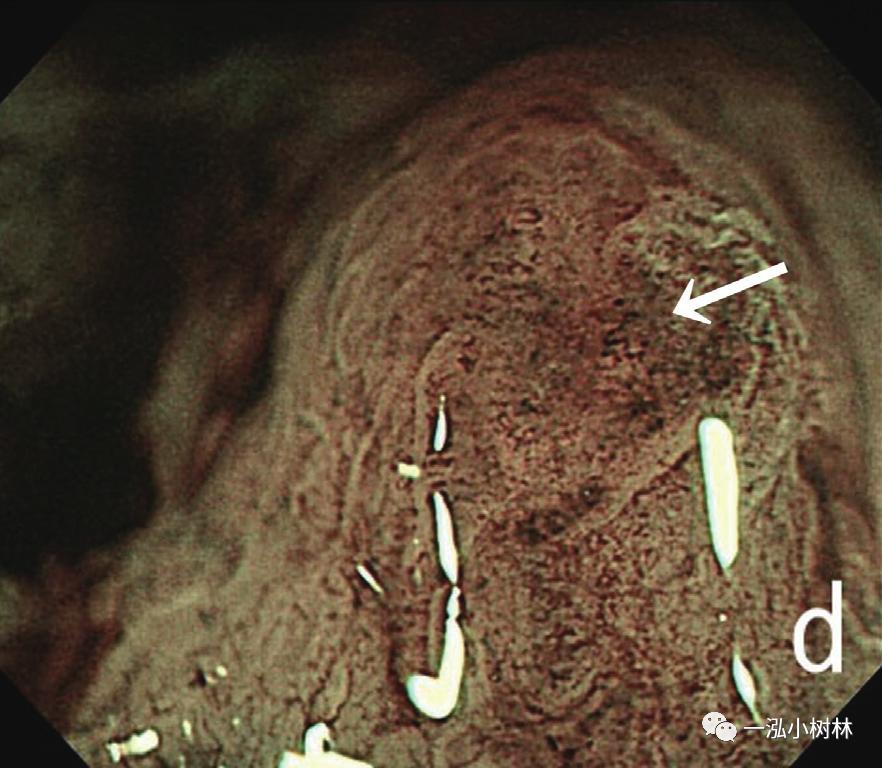

内镜检查(图1):胃黏膜整体粗糙、弥漫性隆起,易出血。在胃体下部、胃窦部黏膜的粗糙明显,散在小隆起,一部分也发现了较大的隆起性变化。ME-NBI观察即使残留着接近正常的腺管,表面微细结构的消失也很明显,在褪色区域也发现了血管的扩张和蛇行、腺管结构的紊乱。

图1c ME-NBI 胃体下部褪色区域中不能识别白区,微小血管的密度降低很明显(箭头)。(问题:NBI放大表现如何与MALT淋巴瘤鉴别)

图1d ME-NBI 贲门部 白区不清晰,微血管扩张、蛇形,分布不规则(箭头)。

以胃为首的消化道淀粉样变性中,沉积的淀粉样前体蛋白的种类和内镜观察结果有相关性。在AA型淀粉样变性中,淀粉样蛋白沉积在以黏膜固有层为中心的黏膜浅层,一般认为,呈现糜烂和溃疡等黏膜表面变化的情况很多。AL型淀粉样变性中,淀粉样蛋白在黏膜下层和固有肌层的比较深层堆积成块状,在内镜观察中,很多情况下可以看到黏膜下肿瘤样隆起和皱襞的肥厚。在怀疑为SSA型的胃淀粉样变性中,迄今还没有进行NBI放大观察的报告。在本病例中,进行了包括NBI放大观察在内的详细的内镜观察,在胃黏膜的褪色区域发现了散在的小隆起和血管的扩张、蛇形、密度的降低。来自TTR的淀粉样蛋白容易沉积在黏膜下层的小的血管壁上,具有容易沉着于固有肌层和浆膜下层的特征。在本病例中,在NBI放大观察中发现了白区的不明确化。白区显示了在NBI观察中在白色边缘形成的黏膜构造,一般认为NBI光在腺窝上皮的散射导致。在活检标本中(图4),淀粉样蛋白以胃黏膜下层为中心沉积,因此,在淀粉样蛋白沉积部位,NBI光的散射降低,可以认为白区变得不明确。另外,也发现了黏膜表层的微小血管的扩张、蛇行、密度的降低。在活检标本中,黏膜下层没有包含明显的血管结构,另外,本病例没有对H.p的感染进行检索,但由于患者年龄和淀粉样蛋白沉积不太明显的部分的胃黏膜出现萎缩,因此推测伴有H.p感染的可能性很高。在消化道淀粉样变性病中,为了确认识别沉着的淀粉样变性,有必要进行组织活检。如果考虑淀粉样变性应行NBI放大观察是非常有效的。

ME-NBI:腺管不规则、白区不明确化,微血管扩张、蛇形、大小不一(H-260Z)